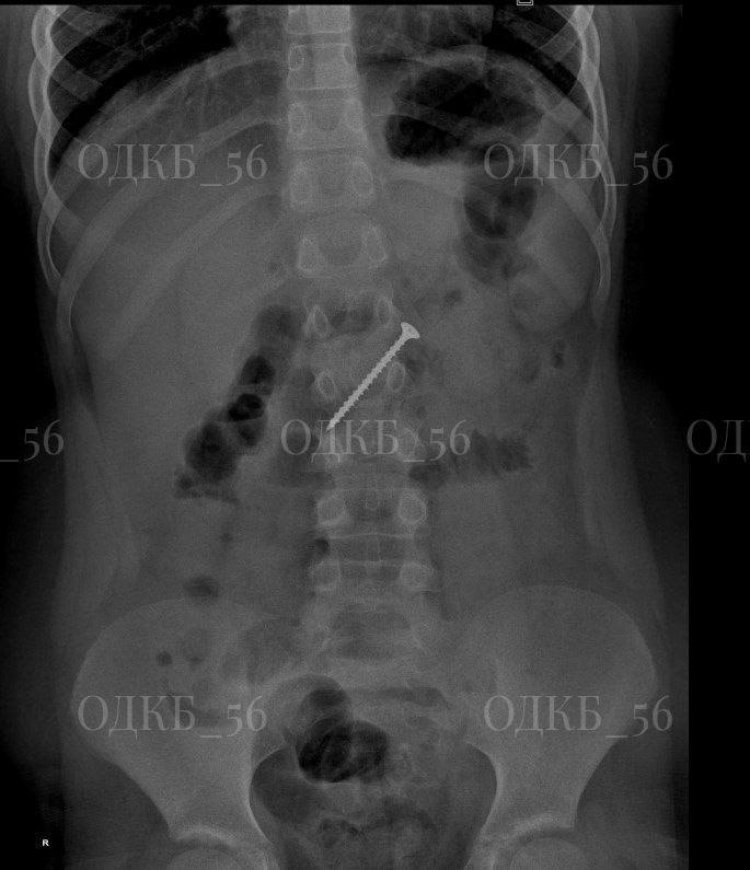

Медики Областной детской клинической больницы спасли жизнь 9-летнего мальчика, который проглотил 5-сантиметровый саморез.

Тревогу забили родители: они заподозрили, что ребёнок проглотил саморез. В центральной районной больнице мальчику провели рентгенографию: в результате обследования выяснилось, что в области желудка есть инородное тело. Пациента доставили в Областную детскую клиническую больницу в Оренбург.

Медики экстренно при общем обезболивании провели эндоскопию верхнего отдела ЖКТ. В двенадцатиперстной кишке специалисты обнаружили мигрированное инородное тело — саморез. Оно представляло угрозу развития кишечной непроходимости и перфорации кишки.

Профессионализм и оперативность медиков спасли мальчика от серьёзных проблем со здоровьем. Саморез удалили. Он оказался большим — 5 сантиметров!